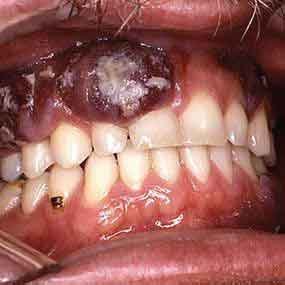

7. Kaposi’s sarcoma

Kaposi’s sarcoma (KS) is a type of cancer that can form in the skin, lymph nodes, or other organs. The skin lesions are usually purple in color

It can occur on the skin and in mucus membranes. For example the moist inner lining of the mouth, nasal passages, and vagina. It occurs among people who have HIV/AIDS.